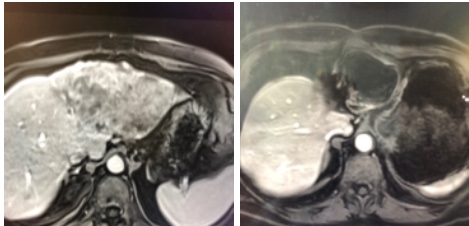

New study @AnnalsofIM bit.ly/2Km3KYu by @DrTalenfeld @WeillCornell: Percutaneous ablation for T1a #renalcancer has similar 5-year survival rates to radical nephrectomy but with far fewer 30-day complications and less #kidneyfailure.